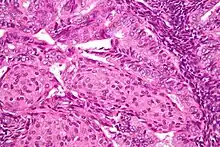

Image of the histology of an endometrioid endometrial adenocarcinoma

Endometrioid endometrial adenocarcinoma—very high magnification—H&E stain

In contrast to endometrial carcinomas, the uncommon endometrial stromal sarcomas are cancers that originate in the non-glandular connective tissue of the endometrium. They are generally non-aggressive and, if they recur, can take decades. Metastases to the lungs and pelvic or peritoneal cavities are the most frequent.[20] They typically have estrogen and/or progesterone receptors.[50] The prognosis for low-grade endometrial stromal sarcoma is good, with 60–90% five-year survival. High-grade undifferentiated endometrial sarcoma (HGUS) has a worse prognosis, with high rates of recurrence and 25% five-year survival.[51] HGUS prognosis is dictated by whether or not the cancer has invaded the arteries and veins. Without vascular invasion, the five-year survival is 83%; it drops to 17% when vascular invasion is observed. Stage I ESS has the best prognosis, with five-year survival of 98% and ten-year survival of 89%. ESS makes up 0.2% of uterine cancers.[52]